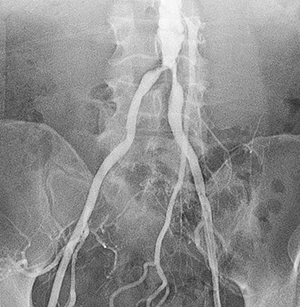

La angiografía periférica es una prueba en la que se utilizan radiografías y un tinte (medio de contraste) para obtener un mapa de los vasos sanguíneos (las arterias) de la parte inferior del tronco, las piernas y los brazos. Dicho mapa puede mostrar si hay obstrucciones en el flujo de sangre.

El proveedor de atención médica introduce un tubo delgado (catéter) a través de la incisión. Luego, guía el catéter hacia una arteria mientras mira una pantalla de video.

Se inyecta el medio de contraste en el catéter para confirmar la posición. Puede que sienta calor o presión en las piernas y en la espalda. Permanecerá tendido sin moverse mientras toman las radiografías. A continuación, le quitarán el catéter.